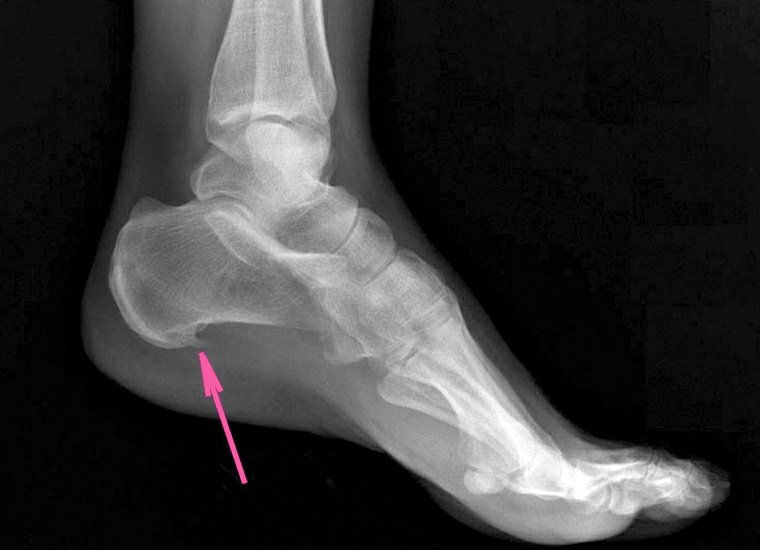

Радиолог избавляет от келоидных рубцов, а также от пяточной шпоры.

- ортопедические патологии, тяжелые травмы и деформации опорно-двигательного аппарата;

- Рентгенография (картинка анатомических структур организма, полученная с помощью рентгеновских лучей). Этот метод до сих пор остается базовым в диагностике поражений суставов и костной системы.